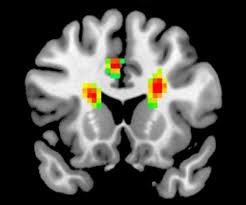

دانشمندان دانشگاه ییل آمریکا و موسسه قلب بریستول انگلستان، ابزار جدیدی را آزمایش کردهاند که خطر سکته و زوال شناختی را در بیمارانی کاهش میدهد که فرآیند تعویض دریچه قلب را تجربه میکنند.

به گزارش سرویس پژوهشی ایسنا، سکته یکی از مشکلات خطرناکی است که حین انجام فرآیند تعویض دریچه قلب transcatheter یا TAVR رخ میدهد؛ این فرآیند تقریبا غیرتهاجمی، برای ترمیم دریچه قلب آسیبدیده و بدون عمل جراحی صورت میگیرد.